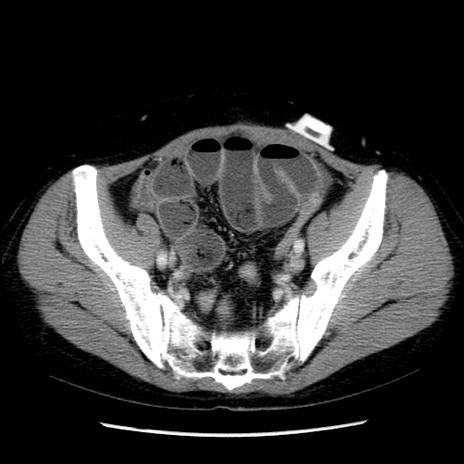

症例6(横断像)

【症例】50歳代女性

【主訴】下腹部痛

【現病歴】本日朝より下痢2回あり。 昼食を食べた後、嘔吐3回、下腹部痛認め、症状軽快せず、当院救急搬送。

最終食事:本日昼(生ものなし)。 昨日の夜、刺身を食ぺたとのこと。周囲に同様の症状の者なし。普段、排便は毎日あるとのこと。

【既往歴】卵巣癌術後(8年前に当院で卵巣摘出)

【身体所見】 意識清明、腹部:平坦、腸蠕動音→、やや硬、下腹部自発痛・圧痛あり、反跳痛あり、筋性防御なし。

【データ】WBC 16000、CRP 0.01